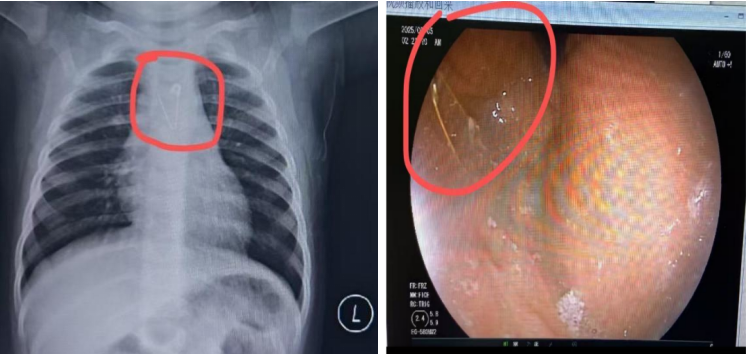

急诊医生随即对患儿进行初步检查,并安排复查X光。X光结果显示,别针位于孩子食道内,针尖部分确实处于打开状态,且异物尚未进入胃部。医生指出,若孩子稍有吞咽动作或出现哭闹,别针极有可能划伤食道,甚至刺破附近动脉,后果不堪设想。

检查过程中,医生小心翼翼地查看患儿消化道内每一处角落,探查食道后未发现异物,便继续进镜。到达胃内时,医生在胃底发现了这枚金色别针异物,随即用异物钳稳稳夹持住异物尾端,缓慢退镜,最终顺利将别针取出,手术过程顺利。